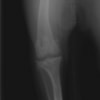

術前左後肢側面像

術前正面像

手術前後のTPA(脛骨高平部の角度)を測定しています。

約29°から約10°へ矯正されています。

術前のTPAは左後肢33.1°右後肢26.8°でしたがTPLO実施により左後肢5.5°右後肢12°に矯正されました。